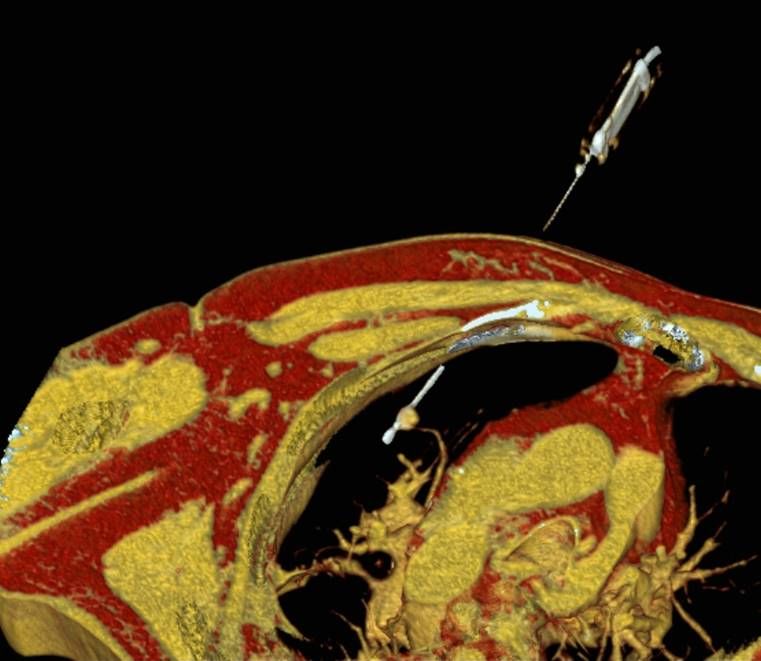

Thermoablation von Nierentumoren

Die minimalinvasive Thermoablation ist auch eine Therapieoption für bestimmte Nierentumore. Damit ein Nierentumor mit einem thermoablativen Verfahren (Radiofrequenzablation oder Mikrowellenablation) effektiv und sicher behandelt werden kann, müssen bestimmte Bedingungen (wie Größe, Anzahl und Lage) erfüllt sein. Dies wird im Vorfeld des Eingriffes mit Kollegen der Urologie besprochen.

Bei der perkutanen Thermoablation von Nierentumoren werden spezielle Applikatoren unter CT- oder MRT Bildgebung in den Zieltumor eingebracht. Durch Hitze wird der Tumor zerstört.